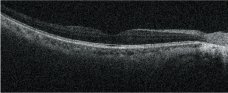

Selectable OCT sensitivity

Selection of the appropriate OCT sensitivity allows acquisition of B-scan images through media opacities.

Ultra-fine

Fine

Regular